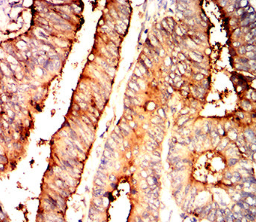

CEACAM6 Mouse Monoclonal antibody[4B9F1]

IHC    1/200 - 1/1000